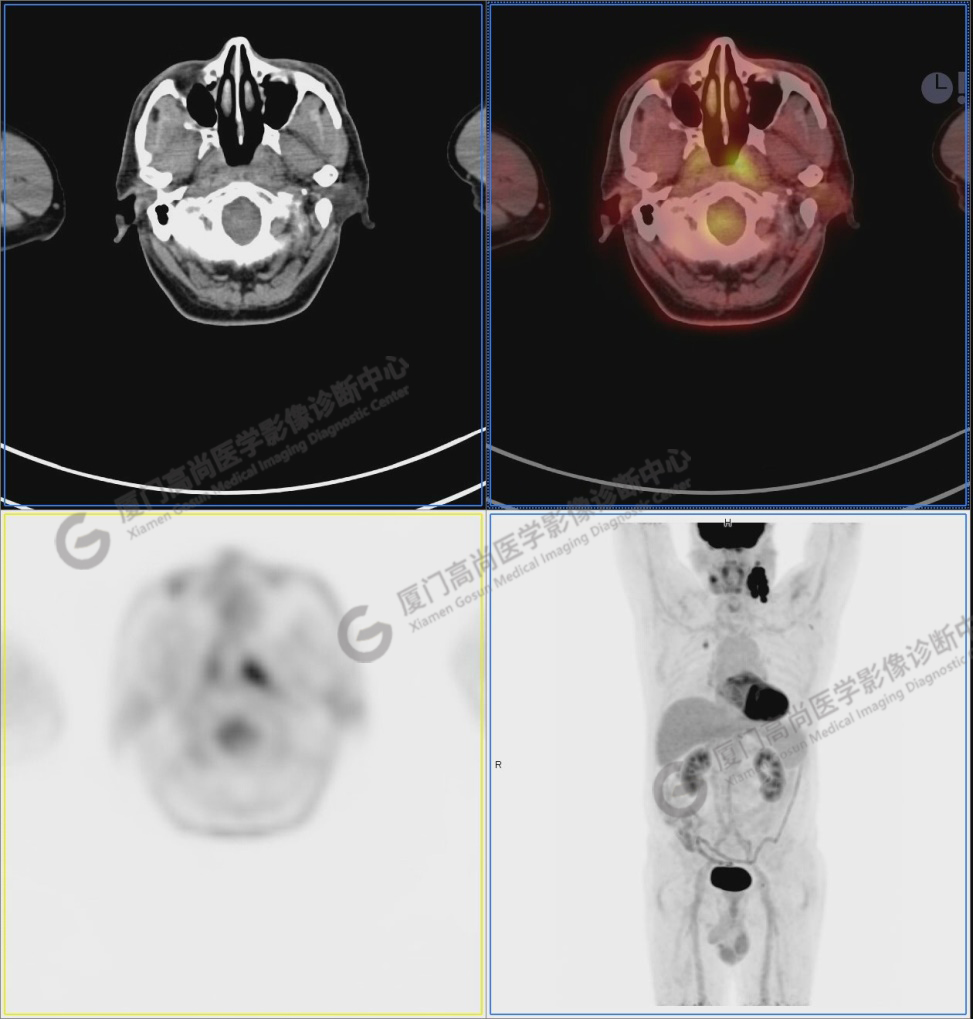

圖1:PET/CT全身圖像

圖2:雙側(cè)頸部多發(fā)增大淋巴結(jié),代謝不同程度增高,考慮為轉(zhuǎn)移。

圖6-9:鼻咽左側(cè)壁增厚,代謝異常增高,考慮為鼻咽癌